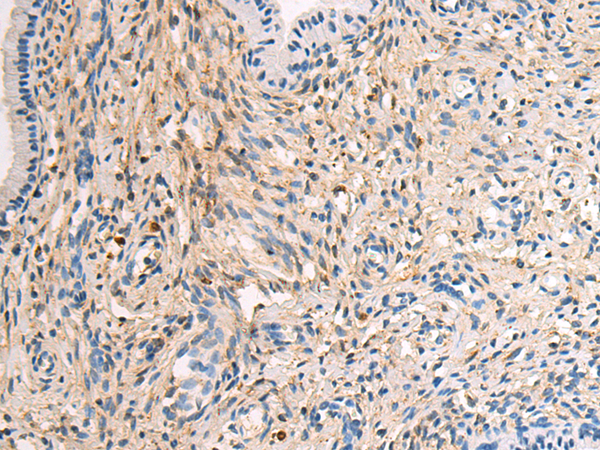

IHC positive control:

Human cervical cancer and Human thyroid cancer

IHC Recommend dilution:

100-500